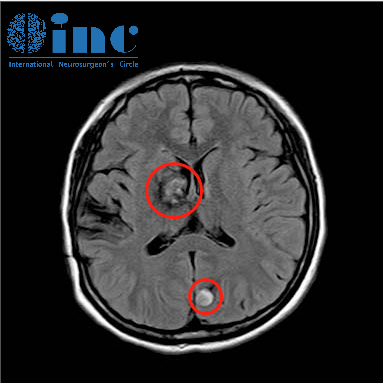

INC出国手术案例之一次出院三周全切多发脑海绵状血管瘤

未满18岁的女孩却有着16年多发脑海绵状血管瘤病史。从出生就开始和病魔进行抗争。这中间经历了四次脑出血,晕厥、癫痫发作伴随了她整个童年青春期的成长。INC出国手术案例之美女高管听神经瘤如何破解“面瘫”魔咒

INC成功出国手术案例之16岁少年巨大基底节胶质瘤赴德手术

“做完手术,我像重新活了一次!感觉自己被赋予了一种前所未有的力量,这种力量让他足以改变世界,不惧生死。”